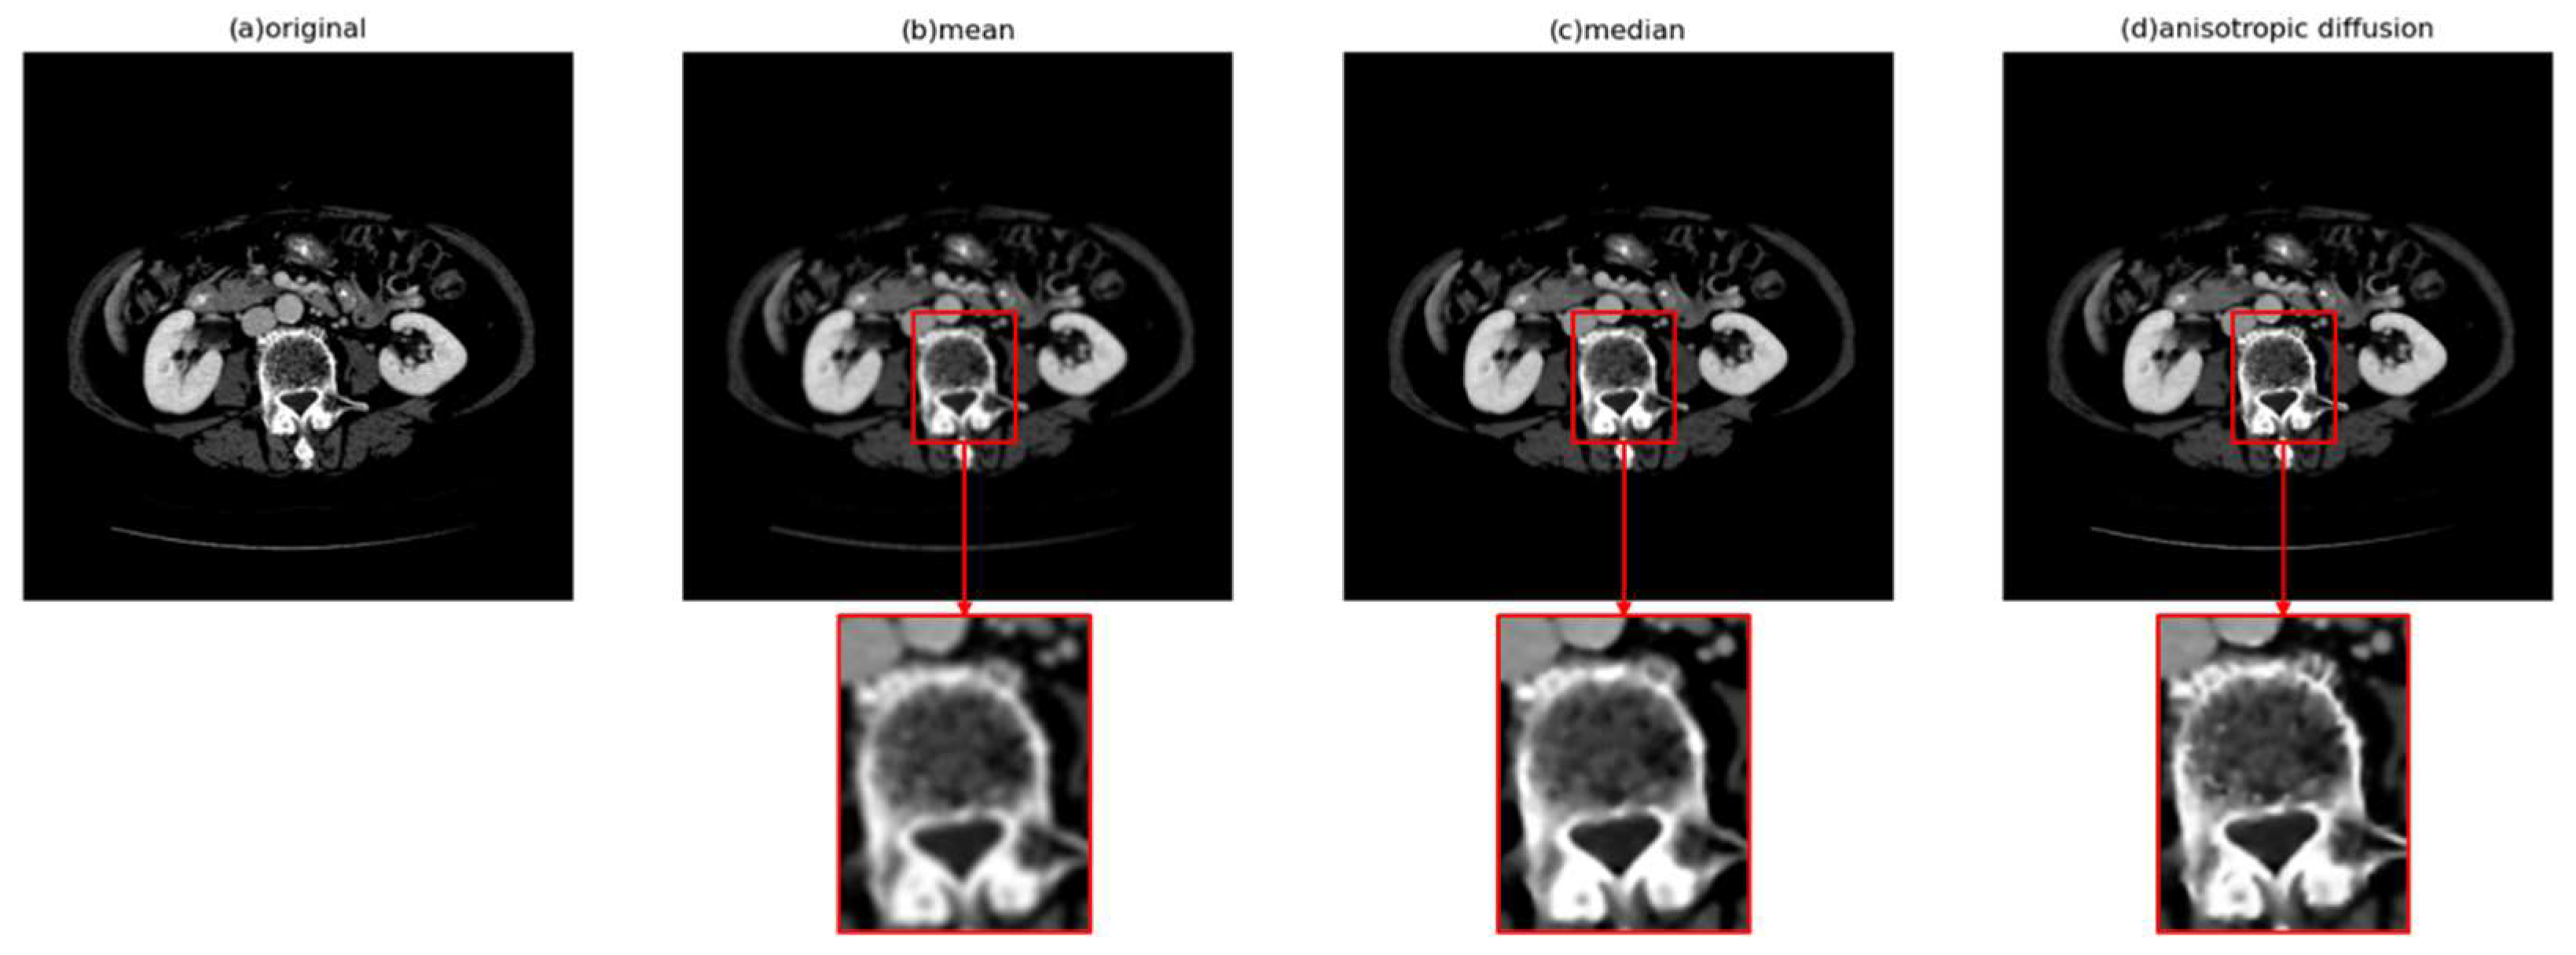

- Digital image enhancement strategies for medical image features: Medical images often contain a high level of noise and details hidden in low-intensity regions. To address this, anisotropic diffusion filters are used for denoising, and histogram equalization is employed to enhance the texture and details of medical images globally. Additionally, the fusion of window level and window width adjustment techniques specific to medical images is applied to target the regions of interest within the image. These strategies aim to achieve global enhancement of medical images while highlighting the desired targets.

3.2. Anisotropic Diffusion